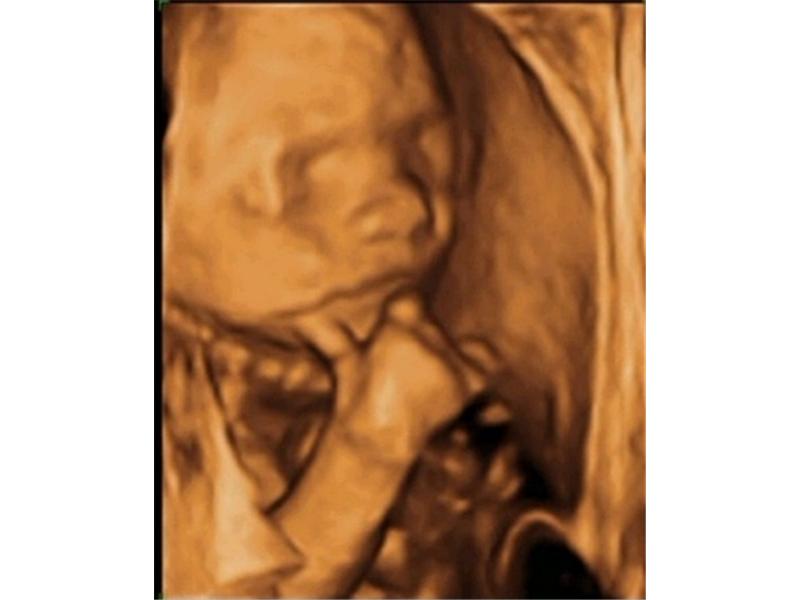

Kluk jako buk